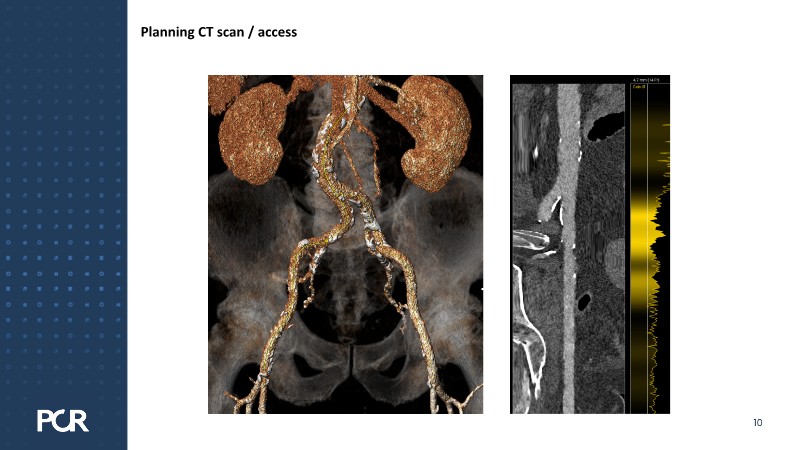

This session examines these crucial aspects through the case of a 77-year-old male with bicuspid aortic valve stenosis, HFpEF and multiple comorbidities, including diabetes, obesity and sleep apnoea.